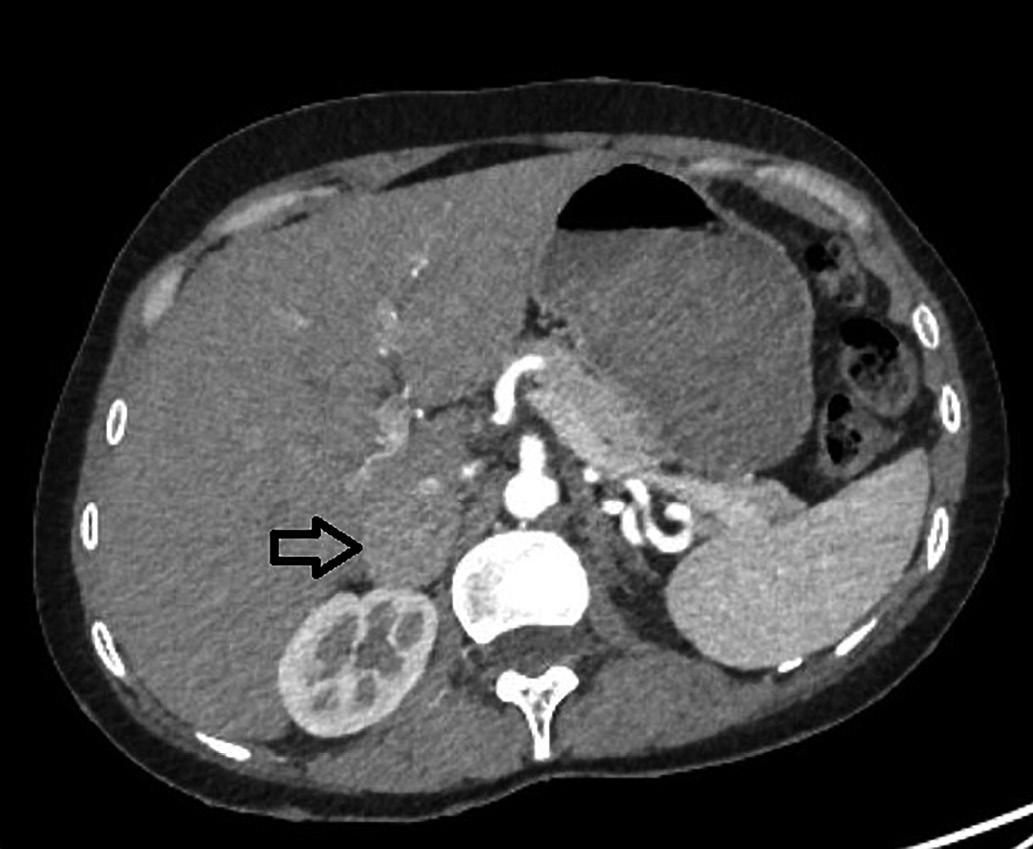

5. Рисунок 5. Мультиспиральная компьютерная томография забрюшинного пространства пациентки С. | |

| Тема | ||